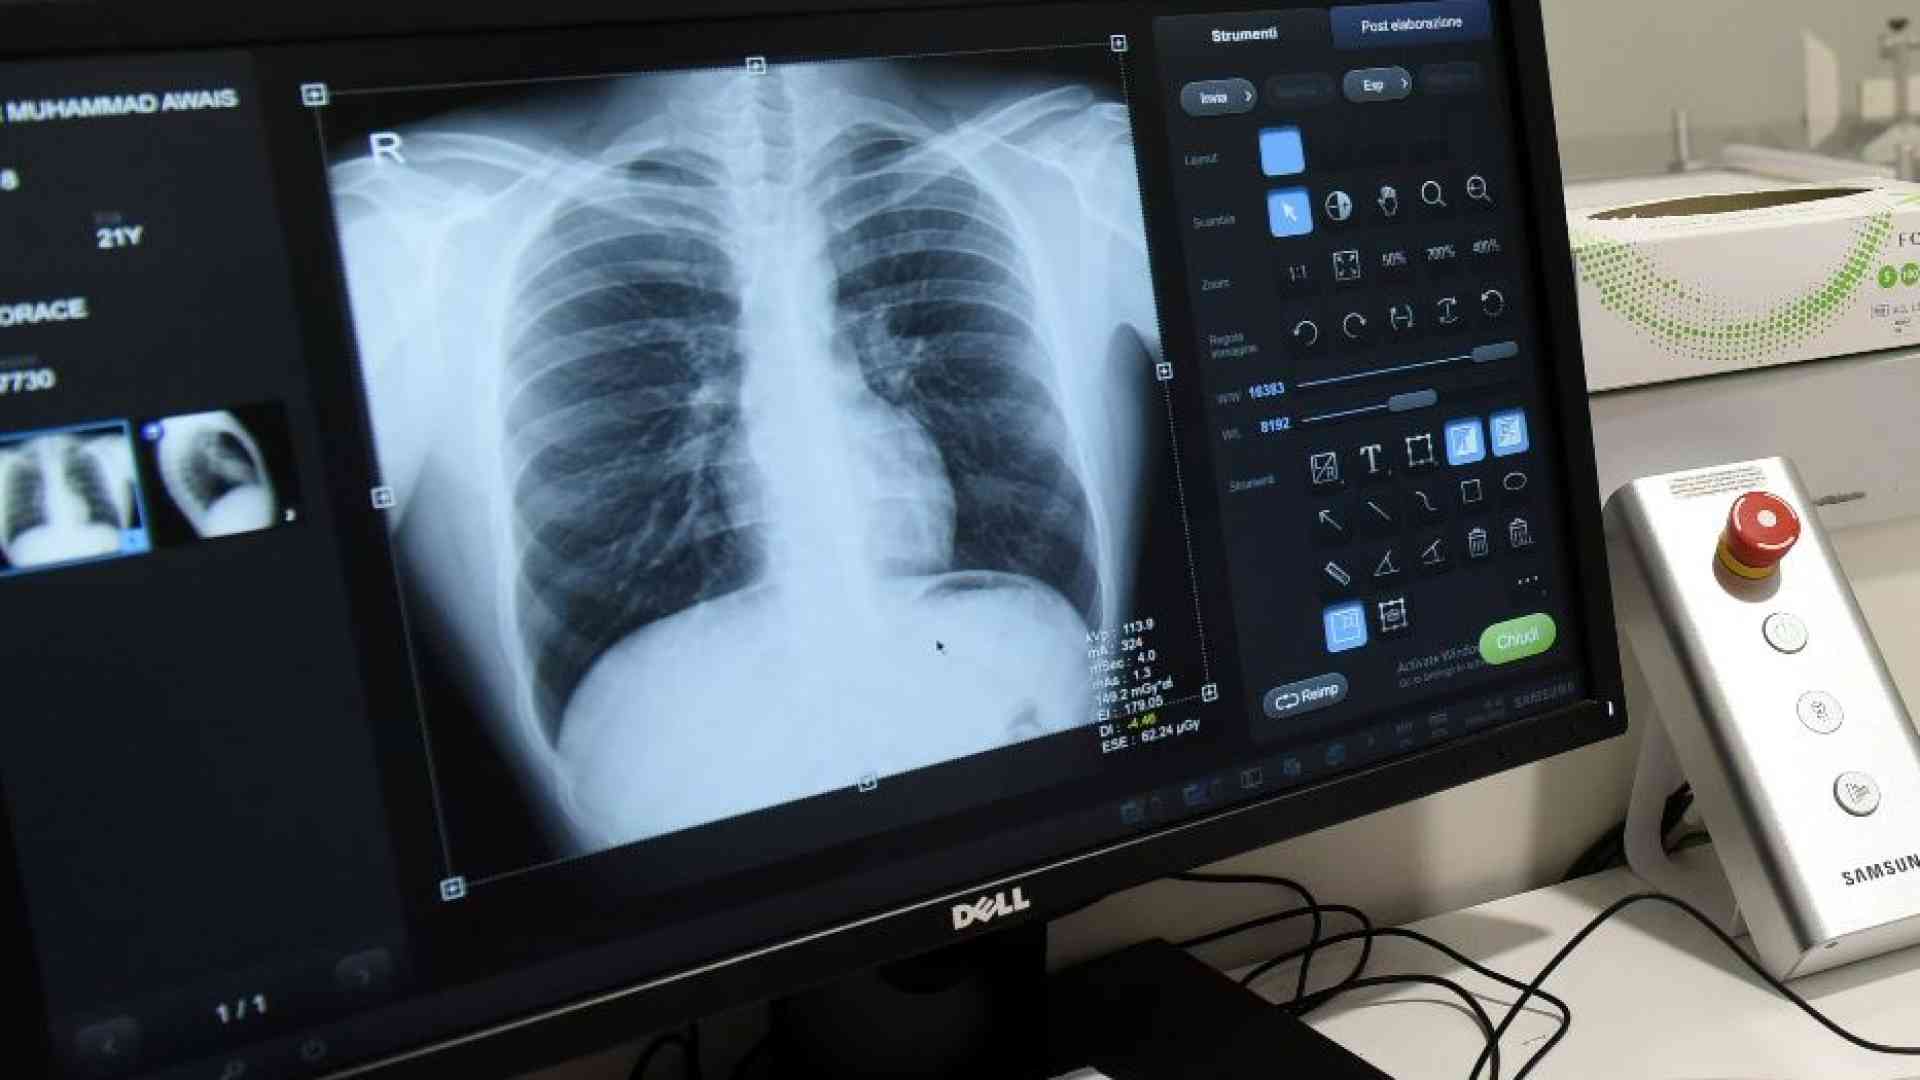

Nuove speranze di cura per tumori al polmone vengono dal congresso della Società americana di oncologia clinica (Asco) in corso a Chicago (Stati Uniti). Sono stati presentati i risultati di due studi clinici dalla azienda farmaceutica AstraZeneca: il primo (Laura) mostra l’efficacia di una terapia mirata contro il carcinoma polmonare non a piccole cellule (Nsclc). Il secondo (Adriatic) quella di una immunoterapia contro il carcinoma polmonare a piccole cellule (Sclc).

Ogni anno, in Italia, sono circa 44mila i nuovi casi di tumore del polmone e per l’80-85% si tratta di tumore al polmone non a piccole cellule (Nsclc). La mutazione del gene Egfr è presente in circa il 20% dei casi.

Il tumore del polmone a piccole cellule (microcitoma) colpisce oltre 6mila persone l’anno in Italia, pari al 15% del totale delle nuove diagnosi di carcinoma polmonare.